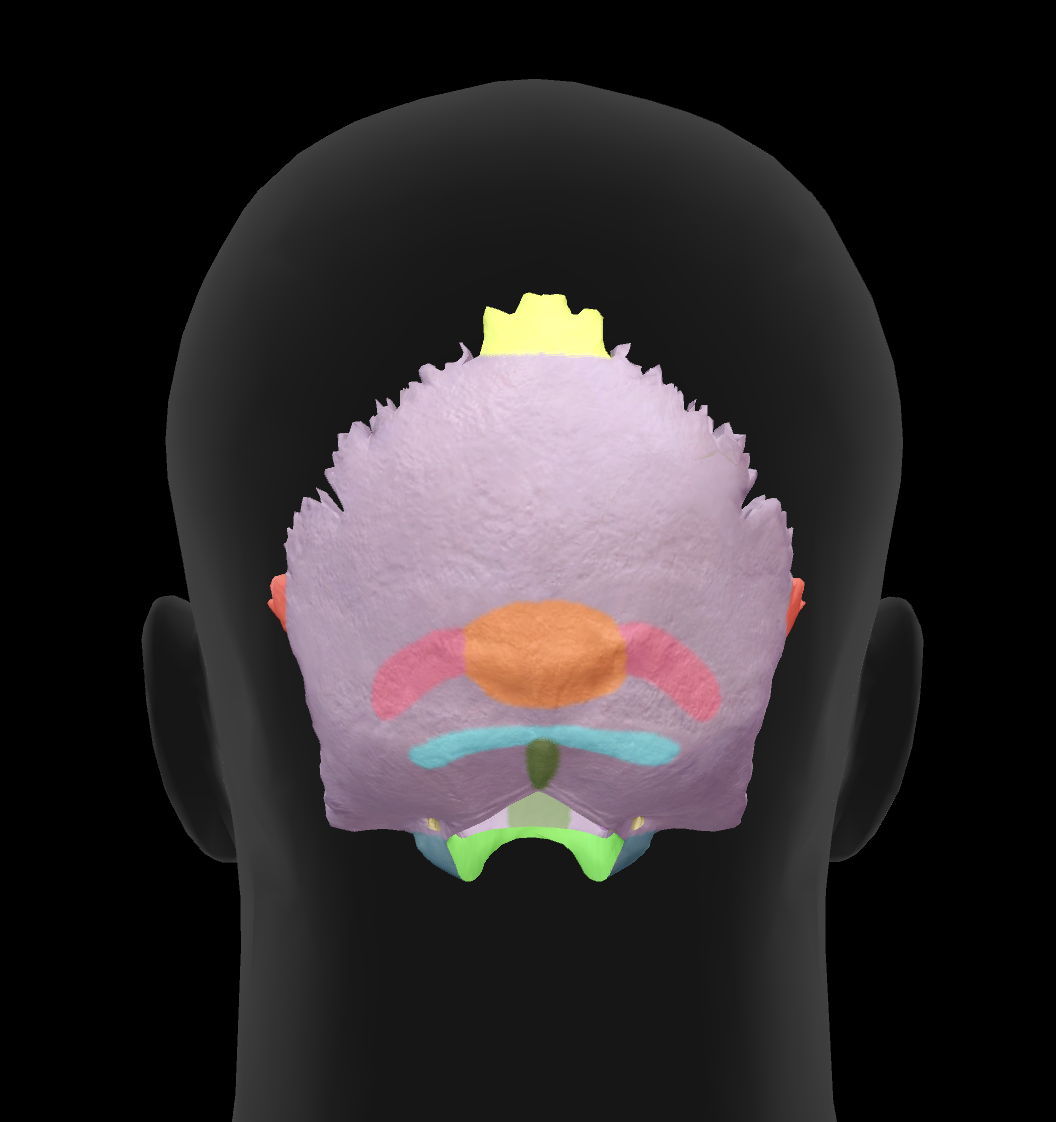

What is bone 2?

parietal bone

What bone is 4?

occipital bone

What is the name of this suture?

coronal suture

What is the name of this suture?

sagittal suture

What is the name of this suture?

lambdoidal suture

What is the name of this feature?

external occipital protuberance

What is the name of this feature?

superior nuchal line

What is the name of this feature?

inferior nuchal line

What is the hole called?

foramen magnum

What is the name of this feature?

occipital condyles